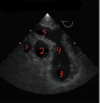

what view is this

transgastric short axis

107

what is 1

LV